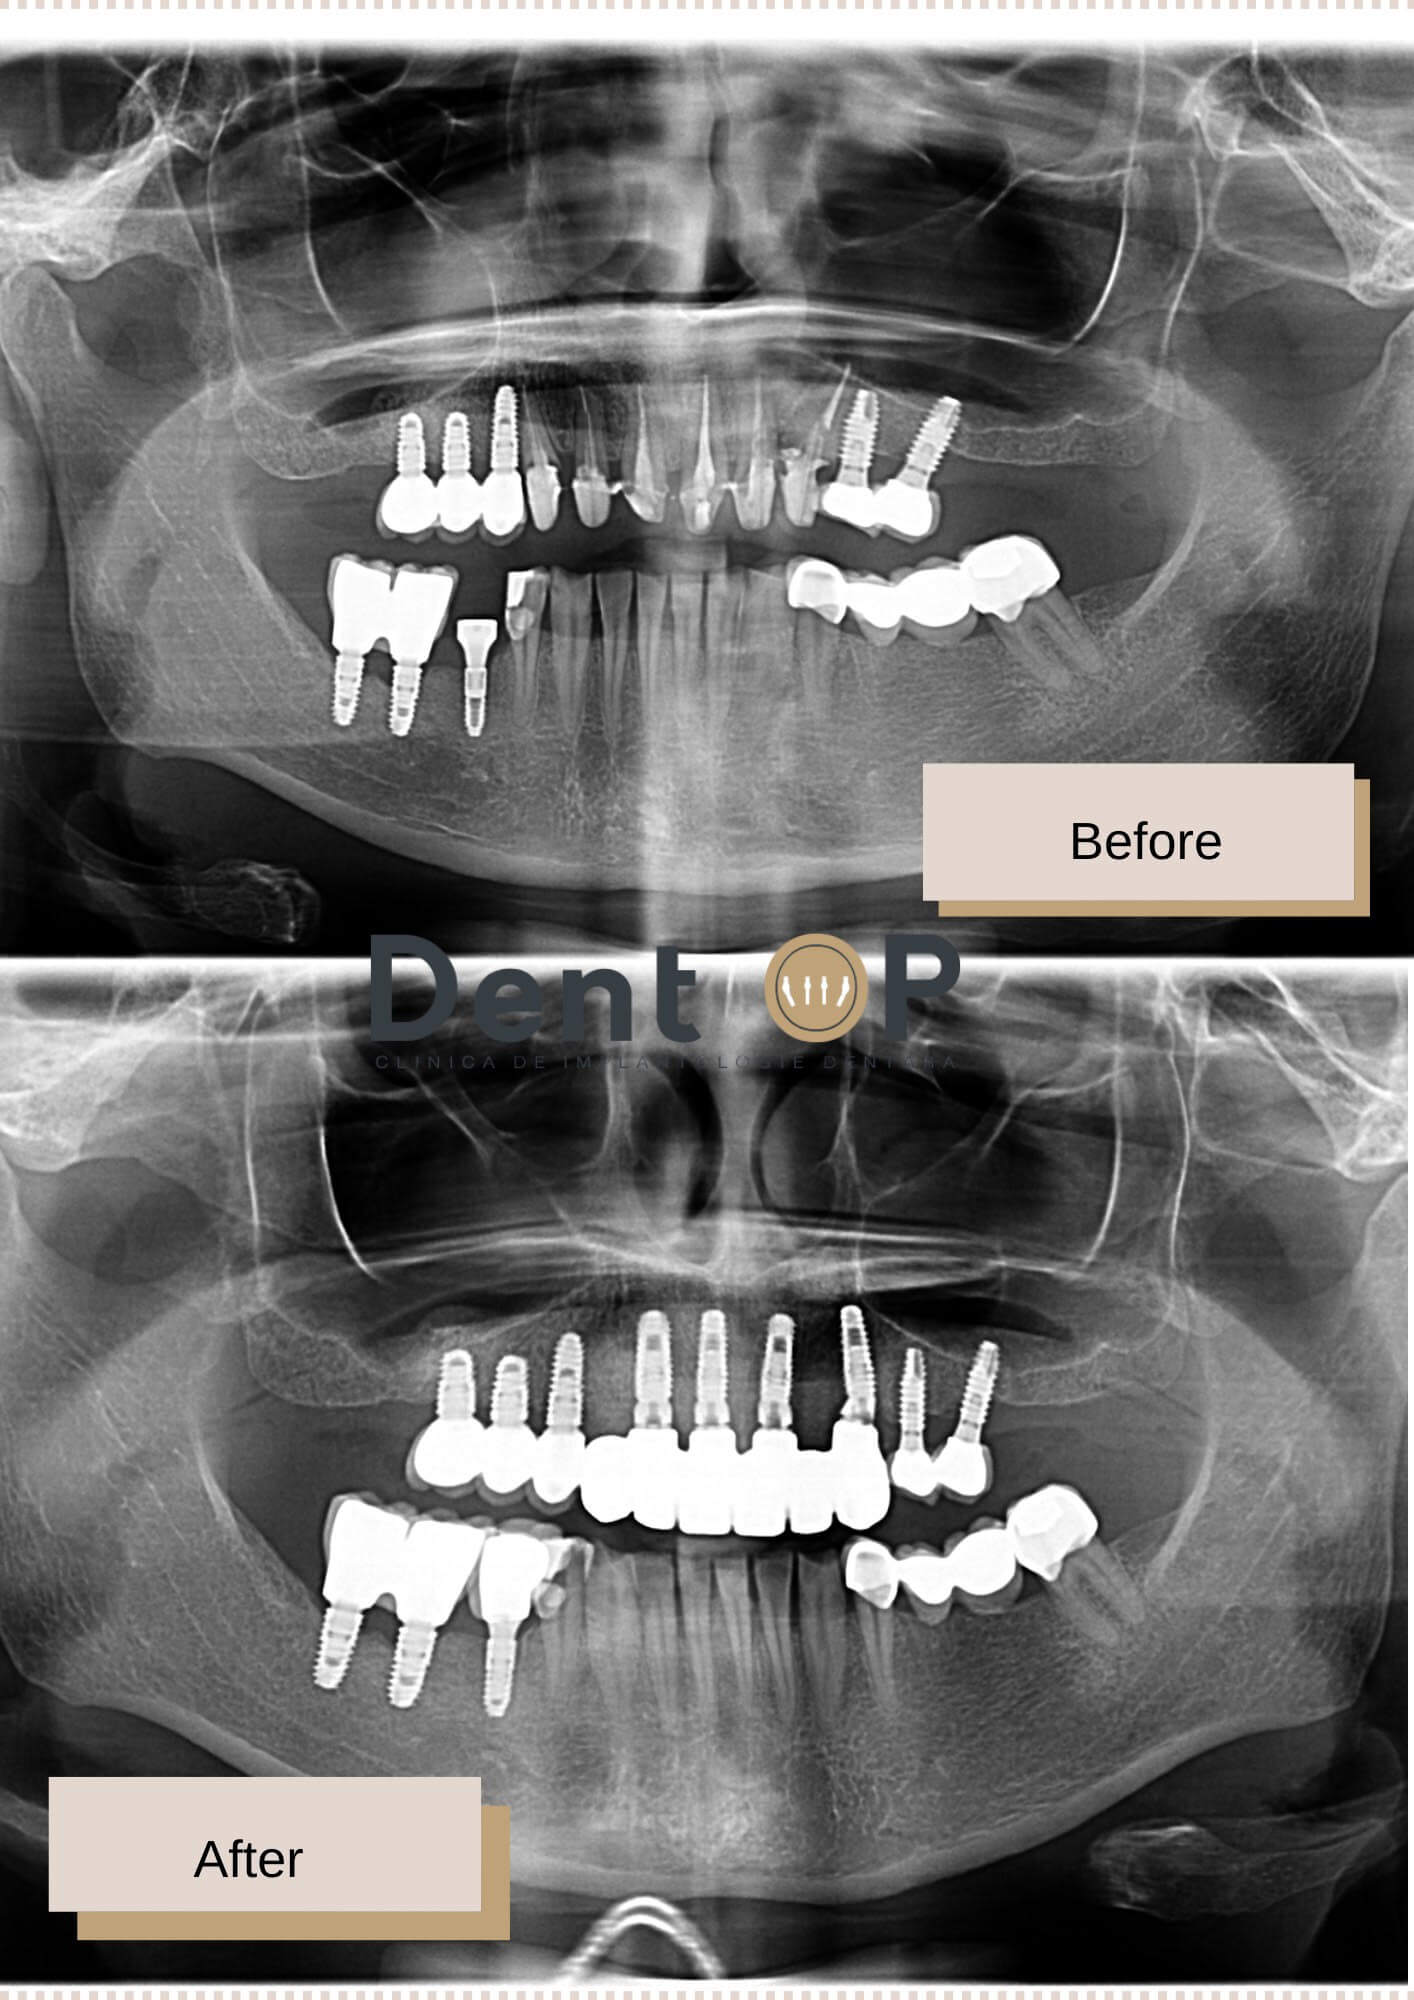

Dr Cazacu Corrado – Medic Specialist Chirurgie Dento-Alveolară i-a propus pacientei tratamentul cu implant dentar. Un număr de 4 implanturi dentare i-au fost inserate în partea frontală a maxilarului. La doar 24h, i-au fost puse și lucrările provizorii pe care le-a purtat timp de 6 luni până la vindecarea completă a gingiei și a implanturilor.

Lucrarea finală i-a fost fixată de către medicul protetician și astfel dantura sa este atât sănătoasă, cât și estetică.